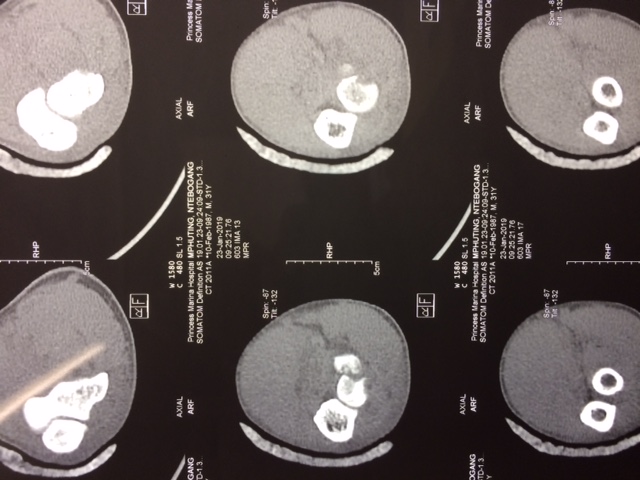

Нужен совет о необходимости хирургического лечения молодого пациента. 2 недели после падения на разогнутую руку. Был в лонгете. Сейчас небольшая боль, движения 20-80 град., пронация и супинация ограничены на 50%. Я склоняюсь в пользу консервативного лечения - продолжить ЛФК, если боль останется , можно позже удалить фрагмент(?- доступ).

Имя     : IMG_3368.JPG

Url     : http://weborto.net:8080/pipermail/ortho/attachments/20190203/d60d8df7/attachment-0001.jpeg